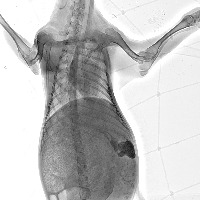

All_goat_ribs Computer Vision Project

Veterinary Diagnostics: Use this model to aid in distinguishing between various animal rib structures, specifically in the case of goats, to diagnose injuries or diseases.

Archaeological Identifications: Assist archeologists and paleontologists in identifying animal remains, verifying whether they belong to a goat based on rib structure.

Education: Enhance veterinary or biology education by providing students with a tool to study and compare different animal skeletal structures, focusing on rib cages.

Zoological Research: Contribute to zoological research and the development of comparative anatomy studies by identifying and categorizing animal bones, in particular, goat ribs.

Food Industry: Apply in the food processing and meat industry to validate the type of meat, particularly in ensuring the sourcing and representation of goat meat.